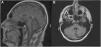

En la exploración neurológica interictal se objetivaron nistagmo horizontal multidireccional no agotable, disartria leve y dismetría dedo-nariz bilateral. Se había solicitado previamente estudio genético de ataxia espinocerebelosa, con resultados negativos para genes ATXN2 (SCA2) y ATXN3 (SCA3). Se revisó RM cerebral, informada como normal, en la que se objetivó atrofia de vermis cerebeloso (fig. 1).

En la AE tipo 2 es frecuente encontrar atrofia cerebelosa vermiana en la RM cerebral, sobre todo en los casos con enfermedades de larga evolución con ataxia interictal persistente que, sin embargo, en ausencia de una sospecha clínica importante, puede pasar desapercibida en un primer momento como en nuestro caso.